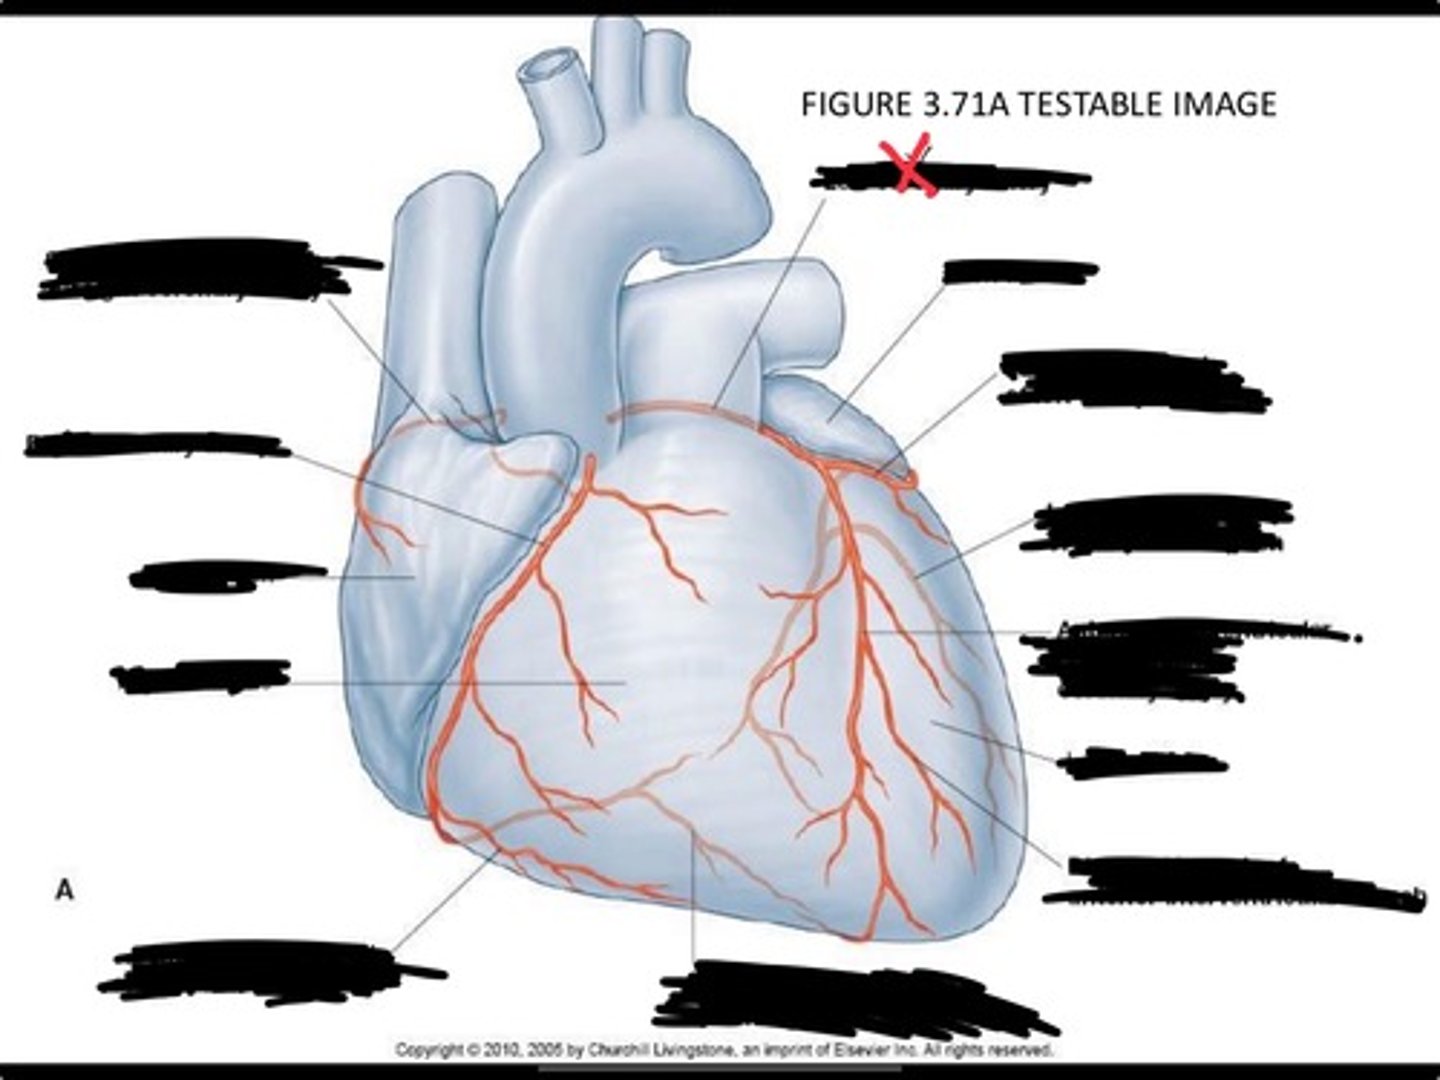

Posterior interventricular branch of right coronary artery

Right arginal branch of coronary artery

Right ventricle

Right atrium

Right coronary artery

Sinu-atrial nodal branch of right coronary artery

Left coronary artery

Left auricle

Circumflex branch of coronary artery